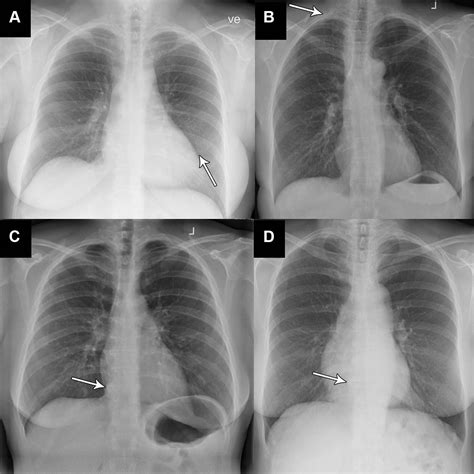

Consolidation

Consolidation refers to the replacement of air in the lungs with fluid, cells, or other material. It appears as an area of increased opacity on the X-ray. Common causes include pneumonia and pulmonary edema.

Pleural Effusion

Pleural effusion is the accumulation of fluid in the pleural space. It appears as a layer of fluid along the chest wall or as a meniscus sign on the lateral view. Common causes include heart failure, pneumonia, and malignancy.

Pneumothorax

Pneumothorax is the presence of air in the pleural space, causing the lung to collapse. It appears as a lucent area without lung markings. Common causes include trauma, spontaneous pneumothorax, and iatrogenic injury.